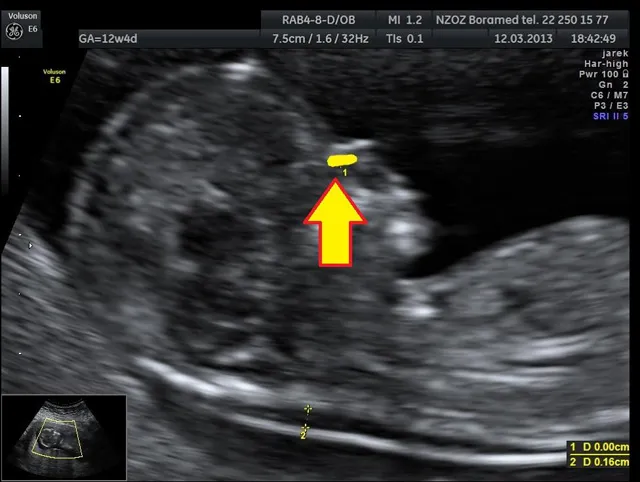

Jednym z najważniejszych badań w pierwszym trymestrze jest USG genetyczne, zwane również USG I trymestru. Wykonywane jest ono między 11. a 14. tygodniem ciąży i pozwala na bardzo dokładną ocenę rozwoju płodu. Podczas tego badania lekarz mierzy przezierność karkową (NT) jest to jeden z kluczowych markerów ryzyka wystąpienia wad genetycznych, takich jak zespół Downa. Oceniane są również inne struktury, takie jak kość nosowa, serce i przepływy krwi. Jest to niezwykle ważne badanie przesiewowe, które pozwala na wczesne wykrycie ewentualnych nieprawidłowości i podjęcie dalszych działań.